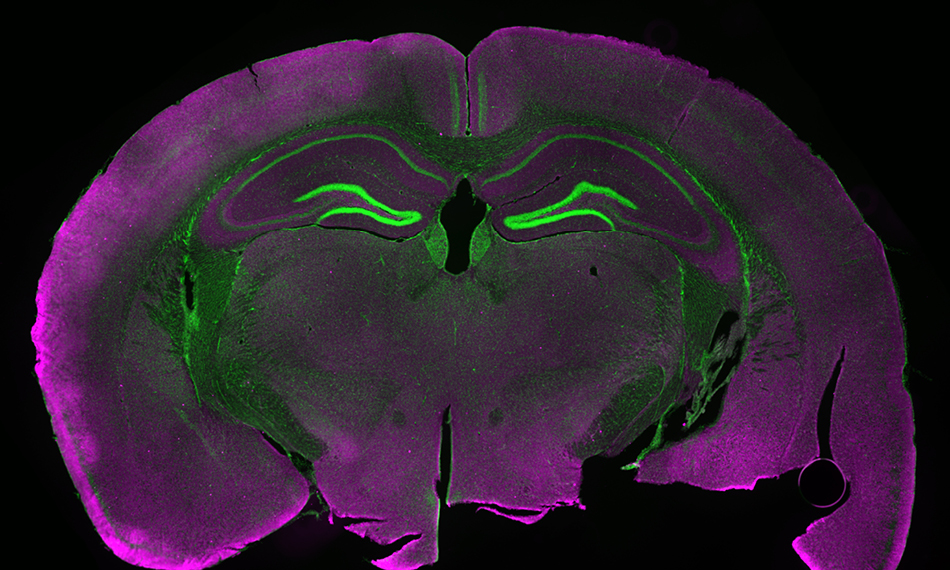

레이저 여기 형광은 많은 현미경 기법, 특히 Confocal Microscopy를 뒷받침합니다. 오늘날 공초점 현미경에는 다양한 변형이 있으며, 대사 또는 신경학적 과정을 실시간으로 추적하기 위해 속도를 높이는 데 초점을 맞추는 경우가 많습니다. 그리고 이제 회절 한계를 훨씬 뛰어넘는 STED 및 PALM/STORM과 같은 몇 가지 초해상도 기법이 있습니다. 하지만 공초점용 저전력 및 높은 빔 품질이 필요하든, 초고해상도를 위한 수 와트의 가변 전력이 필요하든, 광대역 여기용 레이저 소스만 필요하든, 현미경 사용에 있어 Coherent 보다 성능 및 비용면에서 더 다양한 옵션을 제공하는 곳은 없습니다.